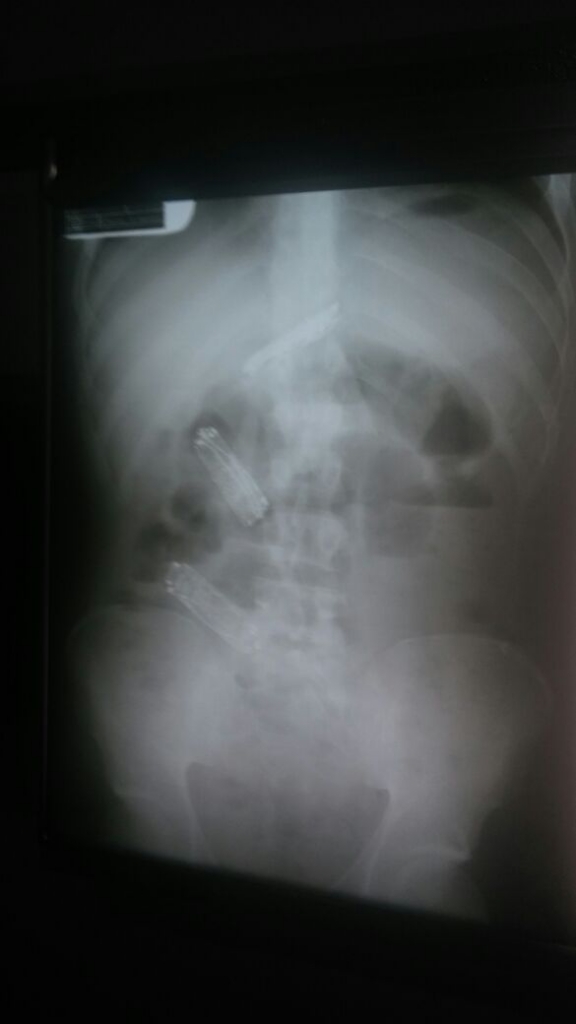

A Secretaria da Administração Penitenciária(Sap) informou que o sentenciado Carlos Augusto Ribeiro Arnaldo, de 26 anos, faleceu no Hospital Regional de Presidente Prudente.O homem teria procurado o setor de enfermagem da Penitenciária “Silvio Yoshihiko Hinohara” de Presidente Bernardes alegando que, no último dia 4 quando houve uma revista geral, teria engolido três aparelhos de telefone celulares no intuito de burlar a vigilância para posteriormente expelir?-los. Depois de uma semana, o reeducando não obteve sucesso em seu plano e estava sentindo fortes dores em sua barriga. Ele foi encaminhado a Santa Casa local, onde foi realizado exame de raio x e constatado que realmente as informações prestadas eram verídicas – os três aparelhos foram localizados em seu estômago.